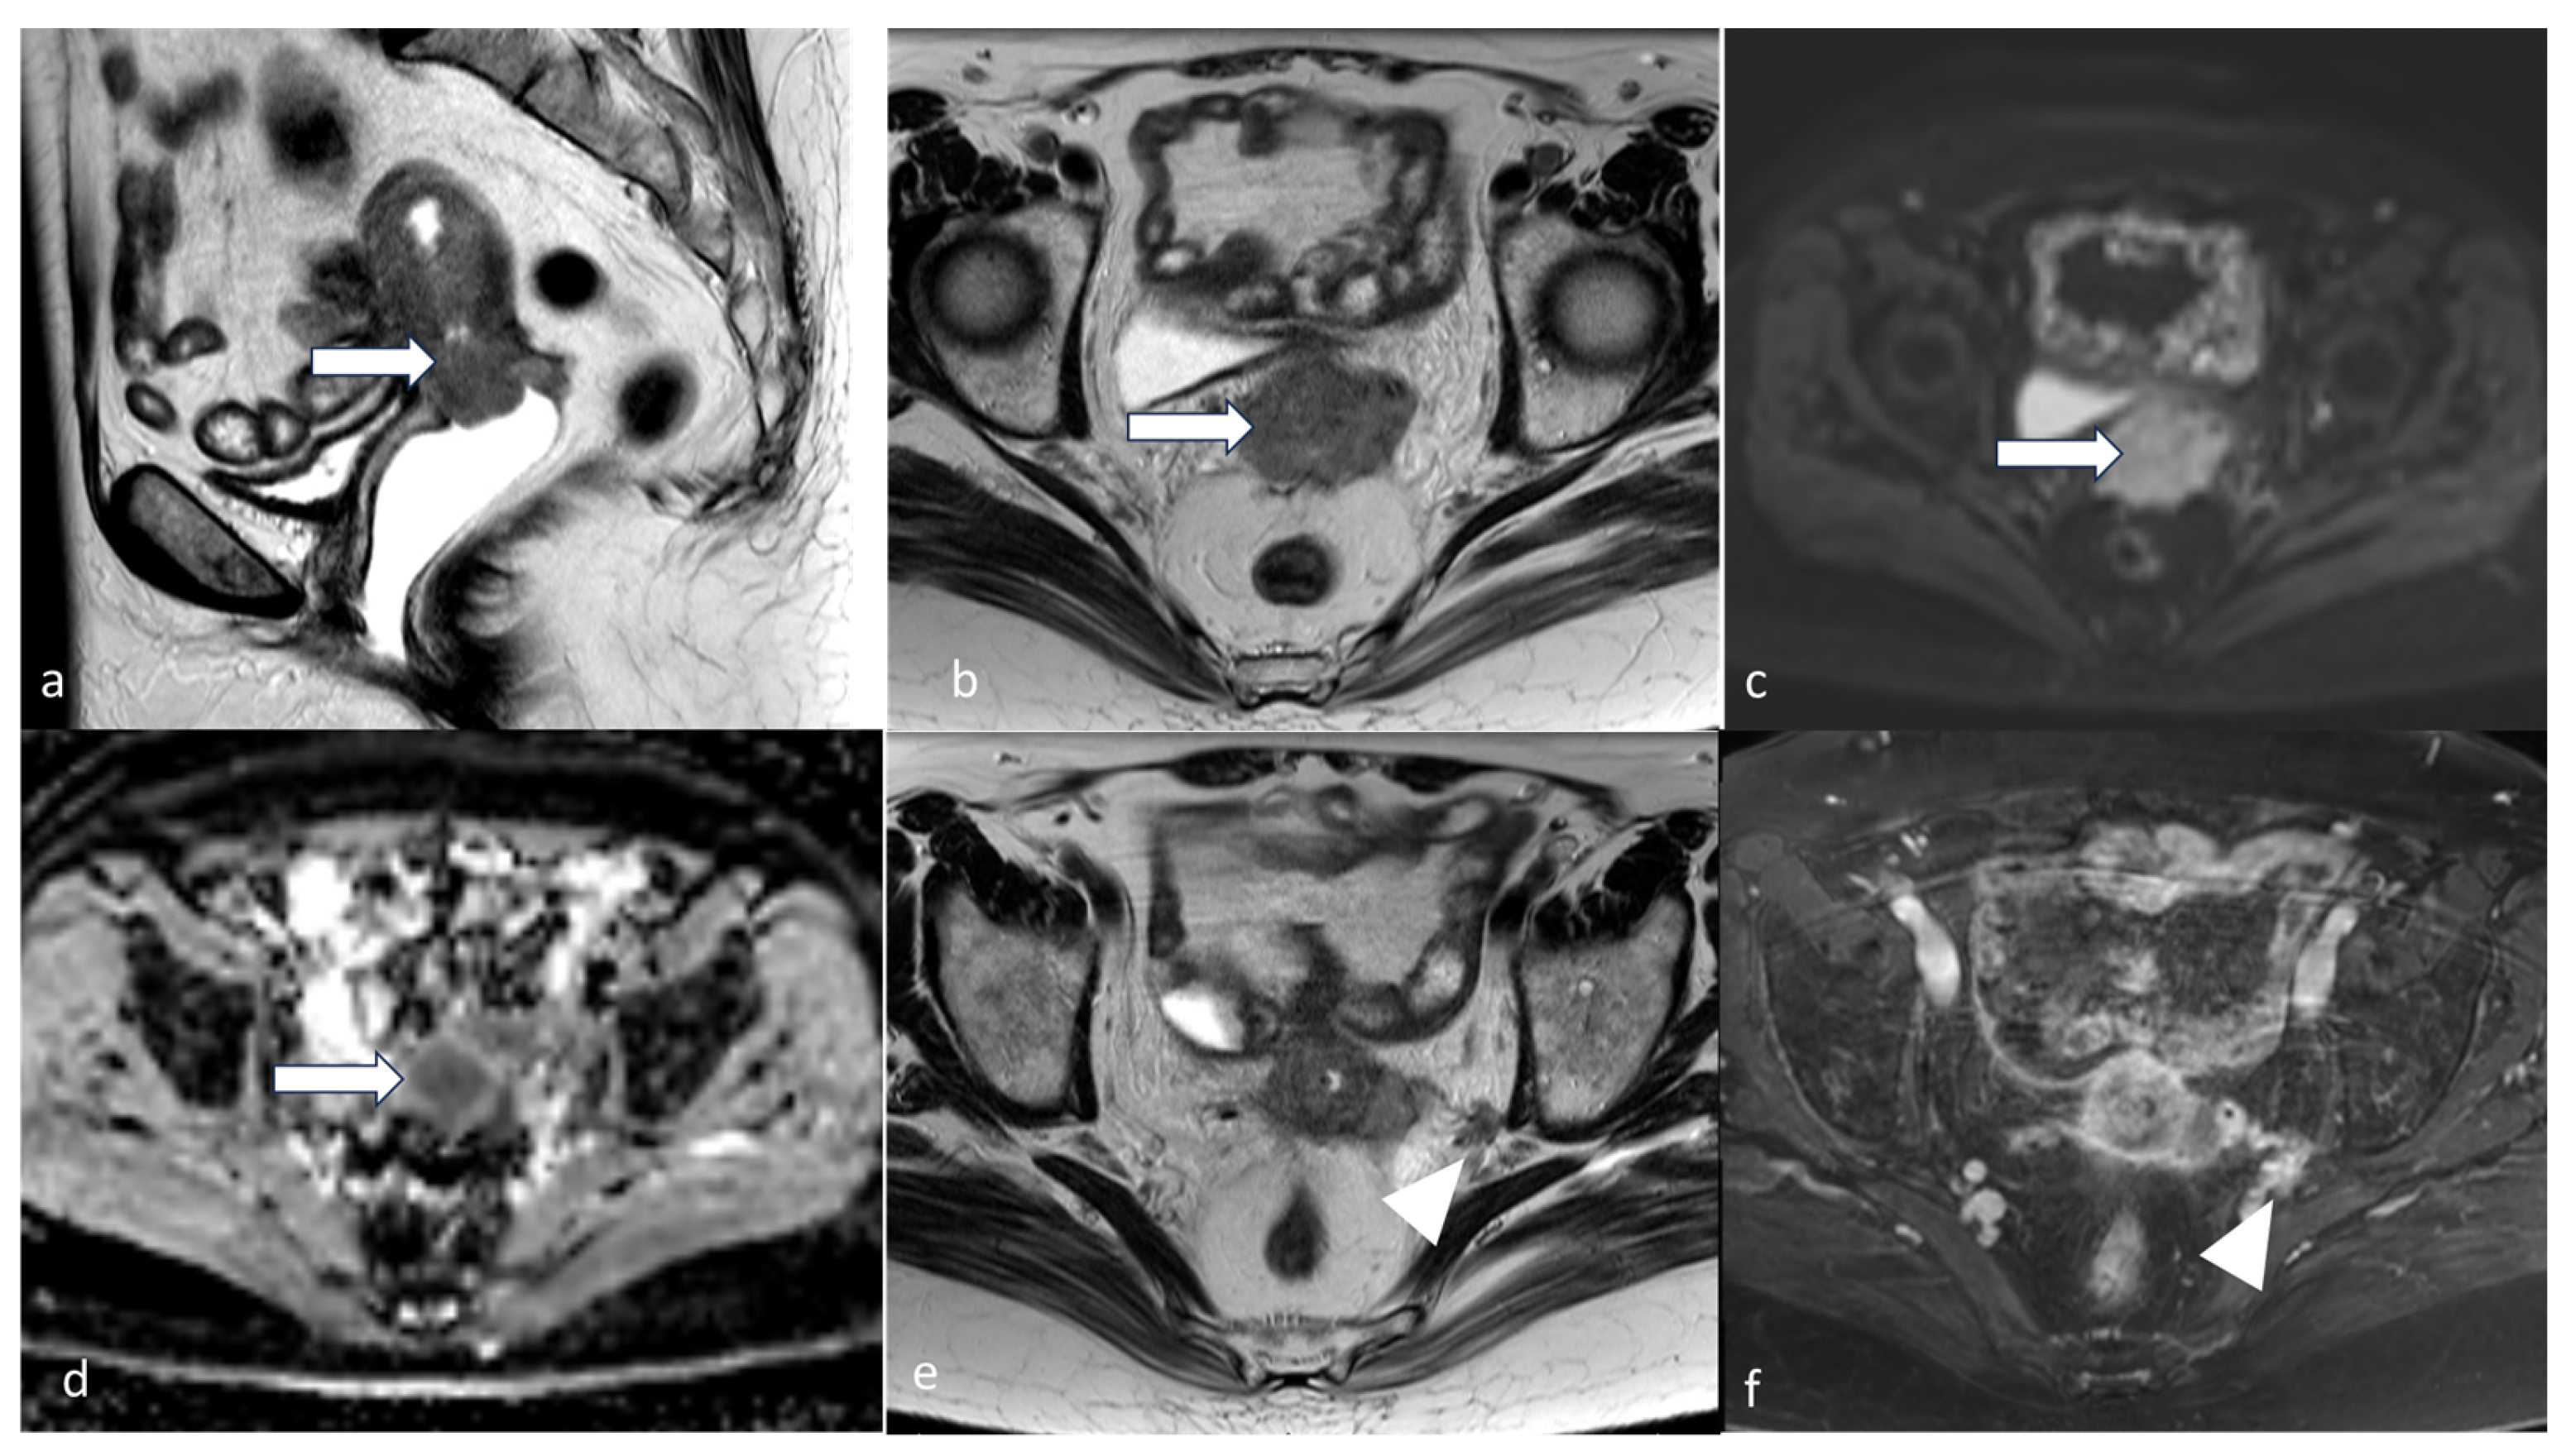

4.3. Stage III

5.3. Magnetic Resonance Imaging (MRI)

- Maheshwari, E.; Nougaret, S.; Stein, E.B.; Rauch, G.M.; Hwang, K.-P.; Stafford, R.J.; Klopp, A.H.; Soliman, P.T.; Maturen, K.E.; Rockall, A.G.; et al. Update on MRI in Evaluation and Treatment of Endometrial Cancer. RadioGraphics 2022, 42, 2112–2130. [Google Scholar] [CrossRef] [PubMed]

- Saleh, M.; Virarkar, M.; Bhosale, P.; El Sherif, S.; Javadi, S.; Faria, S.C. Endometrial Cancer, the Current International Federation of Gynecology and Obstetrics Staging System, and the Role of Imaging. J. Comput. Assist. Tomogr. 2020, 44, 714–729. [Google Scholar] [CrossRef]

- Szadkowska, M.A.; Pałucki, J.; Cieszanowski, A. Diagnosis and treatment of peritoneal carcinomatosis—A comprehensive overview. Pol. J. Radiol. 2023, 88, e89–e97. [Google Scholar] [CrossRef] [PubMed]

- Kyriazi, S.; Kaye, S.B.; deSouza, N.M. Imaging ovarian cancer and peritoneal metastases—Current and emerging techniques. Nat. Rev. Clin. Oncol. 2010, 7, 381–393. [Google Scholar] [CrossRef] [PubMed]